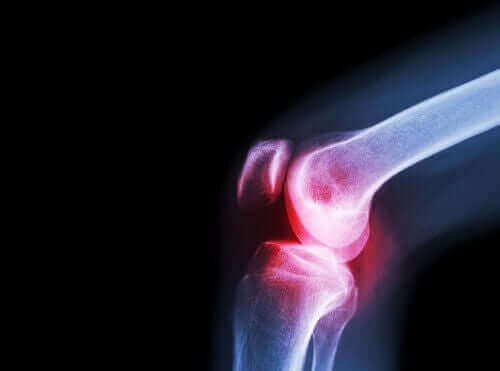

変形性関節症は、関節軟骨を損傷するリウマチ性疾患の一つです。

関節には、滑膜が生成する滑液という液体が含まれており、関節を形成する骨は、関節軟骨で覆われています。

この軟骨が損傷を受けると、痛み、こわばり、機能障害を引き起こします。

変形性関節症の診断においては、関節炎との区別をすることが大切です。

関節炎は、軟骨の摩耗ではなく、関節の炎症が原因で発症しますが、どちらも痛みを引き起こすため、治療においてはどちらの場合にもアセクロフェナクが有効です。